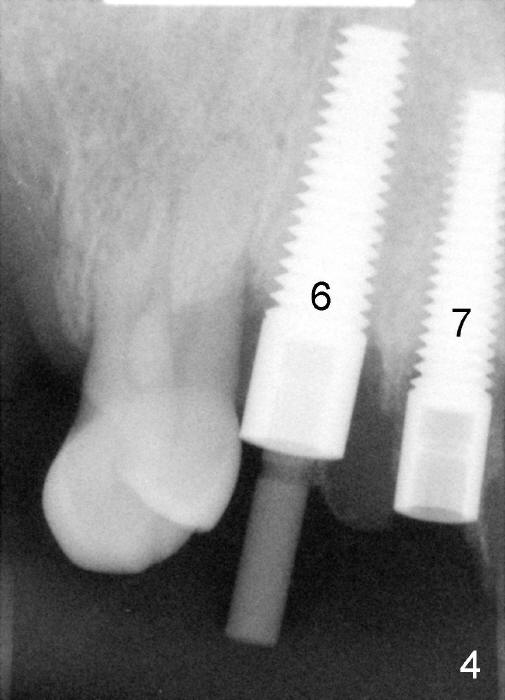

The most severely affected teeth (#6,7 and 9) are extracted and immediately replaced by 4x20 mm (#7) and 5x20 (#6,9) implants (Fig.4,5). Straight (0 degree) uniposts (3 and 4 mm, respectively) are rotated tightly into the wells of the implants by hand screw driver. In order to have reversibility to hybrid denture in the future, these uniposts are not cemented. Heavy retention grooves are placed between the uniposts and implants. Provisionals are fabricated immediately and cemented temporarily. To increase stability, flowable composite is added to the area between the provisionals of #6 and 7.

Fig.6 shows these provisionals 1 week postop. The patient is happy with the result. His diet is confined to soft food. The provisional at the site of #9 is slightly mobile.

Dear Tony and Dr. Borgner: Thanks for the input. The patient showed up today. The provisional of #7 is off (Fig.9) and then recemented and bonded to the provisional of #6 with flowable composite. Open the magnified Fig.9 to see whether the vertical groove is wide and deep enough or not. By the way, the diameters of the implant and of the abutment are 4 and 3 mm, respectively.

The provisional of #9 is still wiggling a little bit buccolingually. It is probably due to loose connection between the implant and the abutment, although follow up PAs do not support it (Fig.7,8; ^: bone graft at the time of immediate implants).